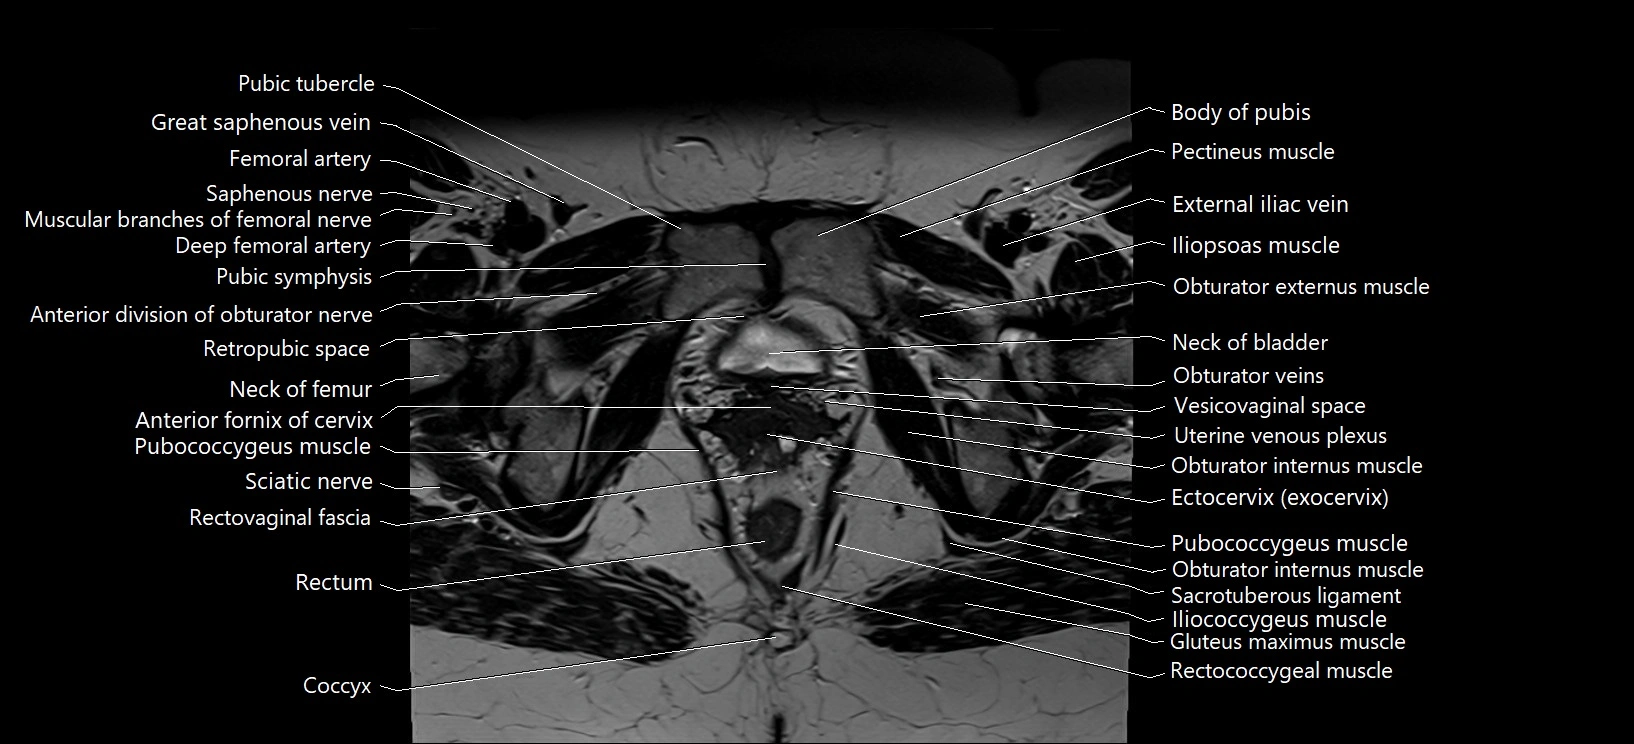

- Body of pubis

- Pubic symphysis

- Pubic tubercle

- Retropubic space

- Neck of urinary bladder

- Obturator externus muscle

- Pubococcygeus muscle

- Sciatic nerve

- Rectum

- Coccyx